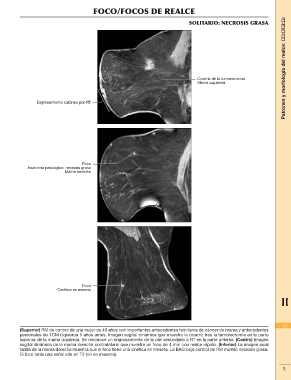

SOLITARIO: NECROSIS GRASA

(Superior) RM de control de una mujer de 49 años con importantes antecedentes familiares de cáncer de mama y antecedentes 53

personales de TCM izquierda 5 años antes. Imagen sagital dinámica que muestra la cicatriz tras la tumorectomía en la parte

superior de la mama izquierda. Se reconoce un engrosamiento de la piel secundario a RT en la parte anterior. (Centro) Imagen 1

sagital dinámica de la mama derecha contralateral que muestra un foco de 4 mm con realce rápido. (Inferior) La imagen axial

tardía de la mama derecha muestra que el foco tiene una cinética en meseta. La BAG bajo control de RM mostró necrosis grasa. 5

El foco tenía una señal alta en T2 (no se muestra).